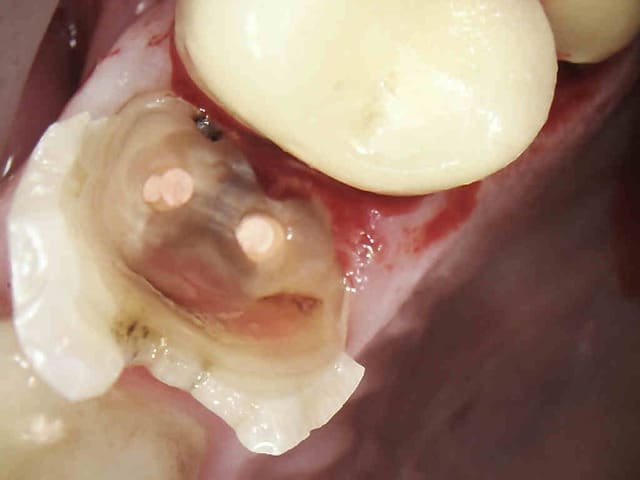

J'ai un de mes patients du cabinet où je travaillais avant qui m'a contacté car il a une reprise d'infection sous la CCM sur 46. Le praticien lui a déposé la couronne et va entreprendre le retraitement endodontique. Puis réaliser une nouvelle couronne. Etant donné que cela fait 3 ans que la couronne est posée le patient est mécontent. Il m'a appelé pour savoir s'il était possible d'avoir une indemnisation.

Je vous mets les photos en pièce jointe.

Ton endo était pas mal.

C'est étonnant que le matériau d'obturation qui était dense en 2011 se soit dégradé à ce point et si vite.

Il est possible qu'il y ait autre chose (perfo latérale un peu en dessous du plancher, fracture de la racine MV).

Pour moi jusqu'à preuve du contraire c'est un alea.

Par contre à ta place je ne contesterais rien du tout, t'es en tort à 300%. J'espère pour toi que toutes tes endos ne sont pas comme ça. Certains me diront que je suis sévère blablabla "ça t'es jamais arrivé de rater" etc, mais en sortant de la fac faire ça je trouve ça honteux.

Mets au moins un cône un minimum calibré. La gutta ne "disparaît" pas.

il peut la reprendre comme il veut l'endo , elle parait cuite la dent. ça a l'air multifactoriel ce truc avec une tres tres grosse composante occlusale .

Completement d'accord avec enlaye pour le multifactoriel ;l'infection est inter radiculaire , suite a une recession parodontale importante ,il suffit de voir la radio. Le retraitement (avec ou sans digue, :-)) est bien, mais ne donnera rien de plus!

Pour l'endo, c'est vrai que la disparition du matériaux d'obturation ne plaide pas en la faveur de notre jeune confrère.

La radio post-op du 15/11/2011 semble montrer la présence de cône de gutta dépassant coronairement . L'erreur ne viendrait-elle pas d'une empreinte de l'ic dans la foulée .

la préparation a retiré les cônes laissant le ciment endodontique.